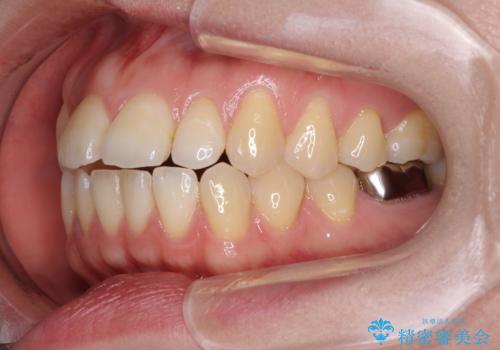

- 唇の閉じにくさを気にして来院された患者様です。

上下左右第一小臼歯4本を抜歯し、ワイヤー装置にて口元を引っ込めるよう矯正治療を行うこととしました。

骨格的に下顎がやや前方にあるため、横顔のシルエットが著しく変化することはありませんでしたが、口元はスッキリと引っ込み、唇が閉じやすくなりました。